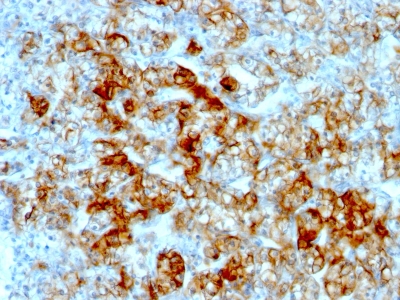

Monoclonal Antibody to Anti-Involucrin Antibody(Clone: SY5)

Figure 1: Anti-Involucrin antibody(39-1063). IHC(P): Human Lung Cancer Tissue.

Involucrin is a keratinocyte protein that first appears in the cell cytosol, but ultimately becomes cross-linked to membrane proteins by transglutaminase. The gene consists of 585 amino acids, 390 of which form a central decapeptide repeat, rich in glutamine and glutamic acid. The involucrin gene, encoding a protein of the terminally differentiated keratinocyte, is polymorphic in the human. Involucrin has previously been mapped to chromosome 1q21. The epidermal protein involucrin has been remodeled in the higher primates. And the existence of two populations of East Asian involucrin alleles gives support for the existence of a Eurasian stem lineage from which Caucasians and a part of the Asian population originated.

Western blot : 2μg/ml; Immunohistochemistry(Paraffin-embedded Section) : 0.4-1μg/ml; Immunohistochemistry(Frozen Section) : 0.4-1μg/ml; Immunocytochemistry : 1μg/ml

| Subcellular location: | Cytoplasm |

| Post transnational modification: | Substrate of transglutaminase. Specific glutamines or lysines are cross-linked to keratins, desmoplakin and to inter involucrin molecules. |

| Tissue Specificity: | Keratinocytes of epidermis and other stratified squamous epithelia. |